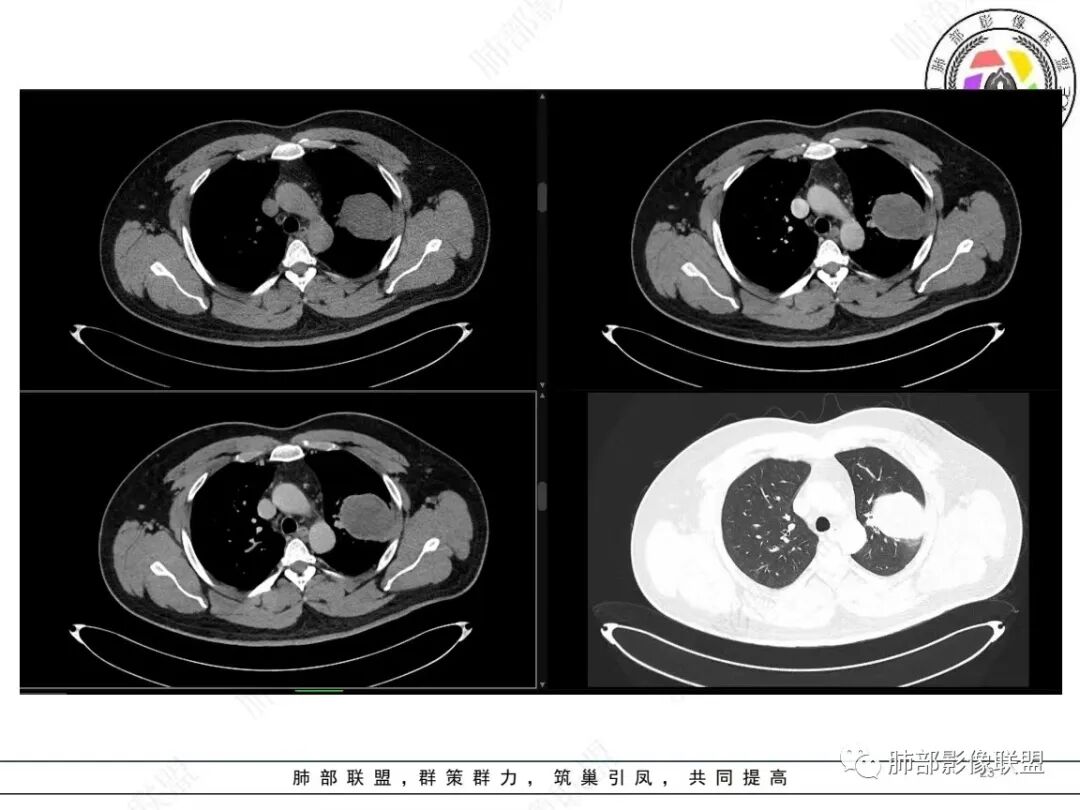

中年人,咳血,左肺上叶实性团块,边界清晰,与胸膜分界不清,可见栽赃表现,病灶推挤支气管及肺血管内移,增强可能条纹血管影,总体强化明显,考虑恶性或交界性肿瘤,间叶组织来源,肉瘤,SFT,肉瘤样癌,滑膜肉瘤。

左肺上叶占位,平扫密度较低,临近胸膜栽赃桩,外向内生长,边缘有膨隆、毛糙,增强后轻度强化,边缘弧线样强化,考虑肉瘤样癌

青年男性,咯血;CT示左肺上叶胸膜下软组织肿块,边界尚清,宽基底与胸膜相连,增强动脉期内见细条状血管影,轻度延迟强化,定位:肺外,胸膜外脂肪存在,考虑脏层胸膜起源;定性:考虑SFT。

影像表现:左肺上叶占位合并出血,胸膜栽赃,边缘强化,局部见血管影,中心密度20Hu,无强化,符合非液化坏死。定位:肺内,定性恶性(明显血管影,栽赃排除错构瘤,中心无强化排除PSP,无明显清楚的坏死边界,强化不符合肉芽肿,排除结核),年龄轻,无长时间吸烟史和肺气肿改变,肉瘤样癌可能性很小,与支气管无确切关系,所以病理类型考虑来源于肺间叶组织的肉瘤,骨外尤文?滑膜肉瘤?

定位肺内明确,来源间叶组织明确,年龄和吸烟史情况排除肉瘤样癌,剩下的就基本上只有骨外尤文和滑膜肉瘤了,再加上强化低,骨外尤文就肯定首先考虑。